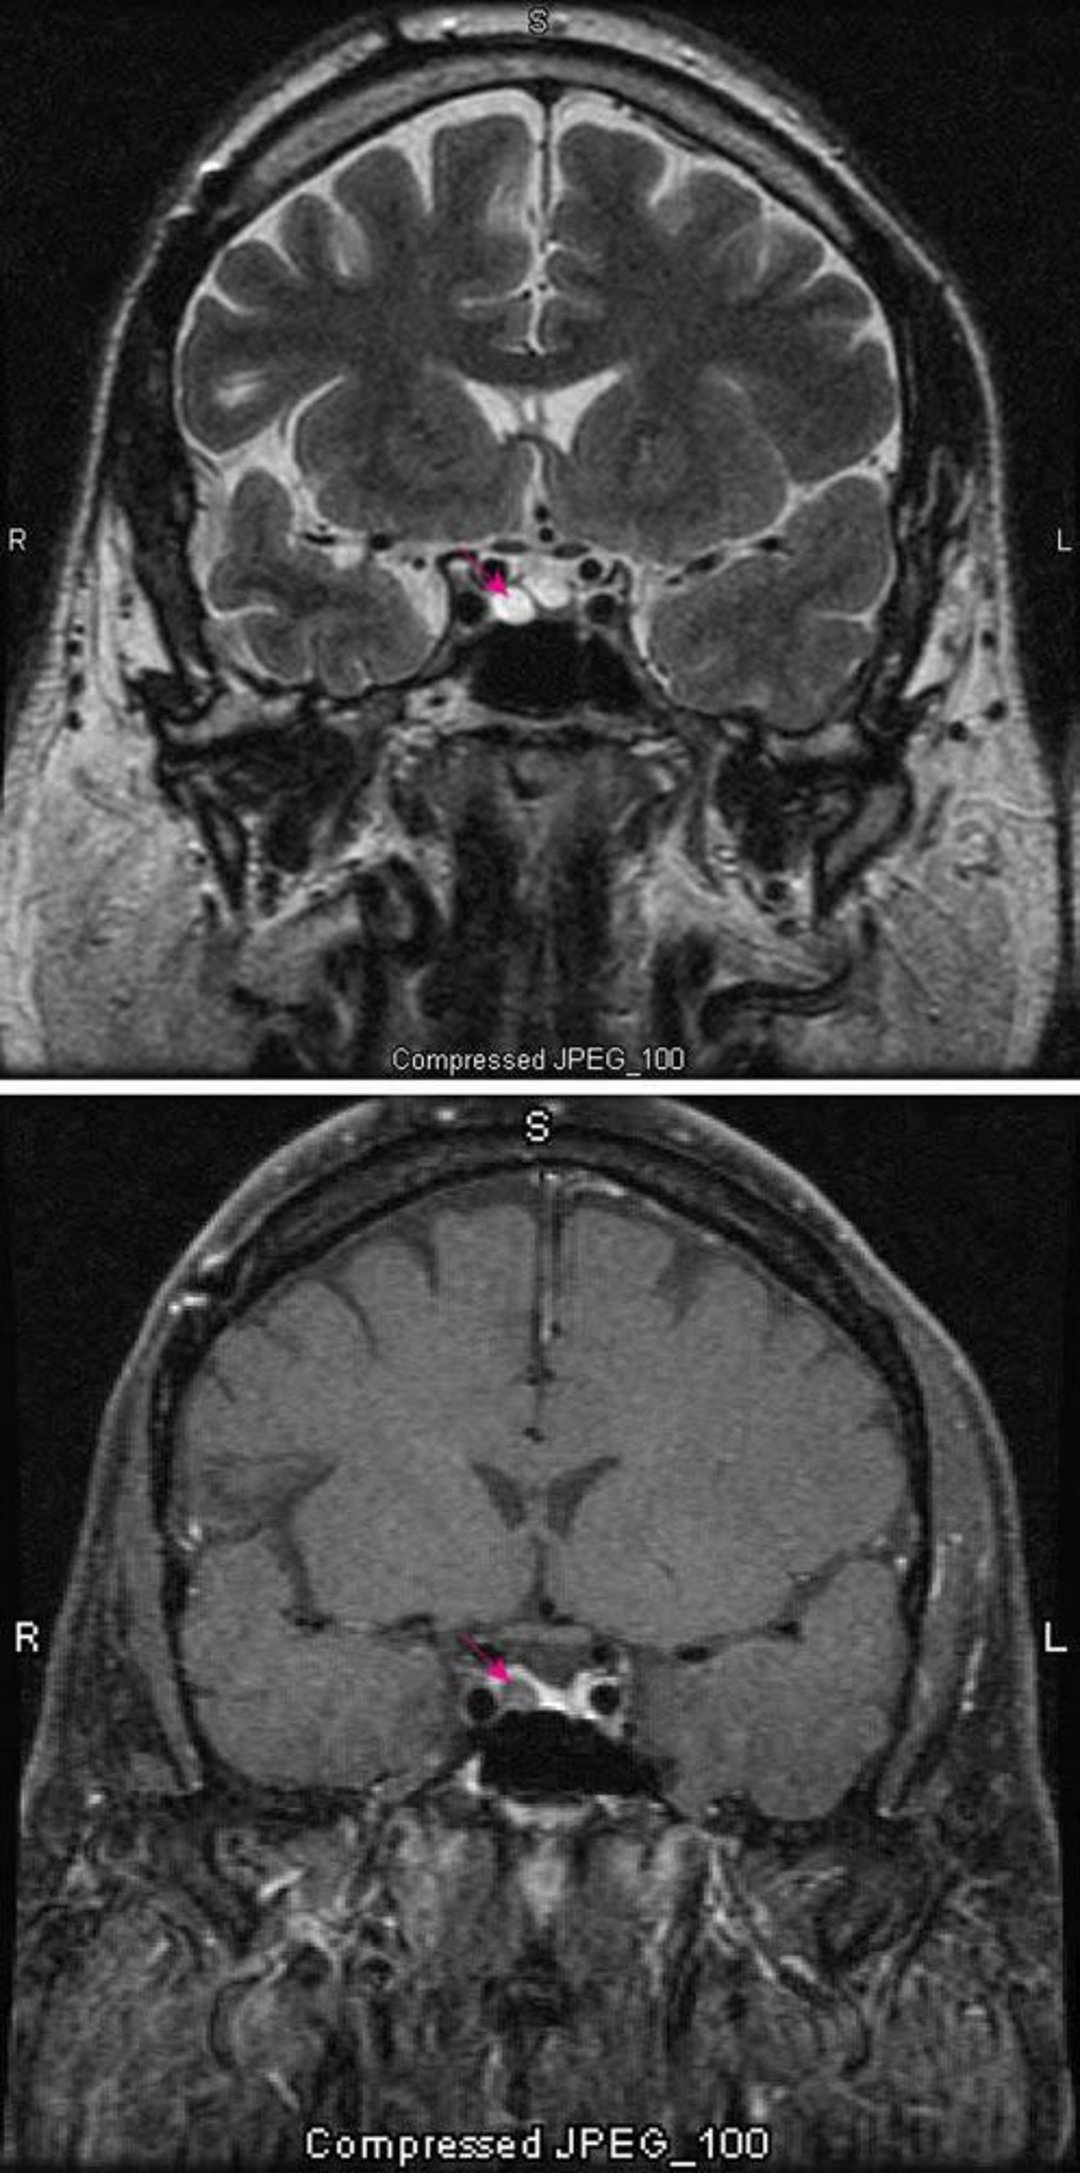

Hypophysen-Mikroadenom

Die T2-gewichtete MRT-Aufnahme (oben) zeigt ein hypophysäres Mikroadenom (roter Pfeil). Der Kontrast (unten) verstärkt normalerweise die Hypophyse (roter Pfeil). Das Adenom erscheint heller.

Images courtesy of William R. Shapiro, MD.